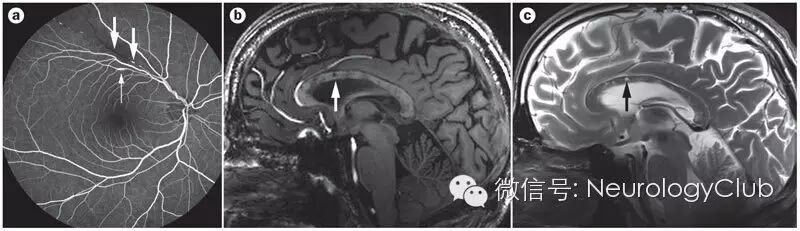

(2)眼底检查:眼底镜检查常可见由BRAO导致的视网膜缺血性苍白色渗出,常为棉絮状,也可见视网膜动脉壁斑块(Gass斑)、弥漫性小动脉狭窄、动脉银丝样改变,后期可见视网膜动脉间侧支循环形成。Gass斑为Susac综合征的特异性表现,典型的Gass斑为黄色,有或无折光性,常远离视网膜动脉分叉处Gass斑可随着疾病的好转而消散眼底荧光血管造影结果可显示视网膜小动脉上细小、局部的阻塞性病灶,即BRAO,是Susac综合征典型的表现,而视网膜静脉一般不受累及。此外,还可以发现特征性的动脉壁高荧光显像(arterial wall hyperfluorescence,AWH),其位置与视网膜分支动脉闭塞位置无关,AWH可以发生于远离BRAO的位置。Martinet等研究发现7例Susac综合征患者急性期的吲哚氰绿眼底血管造影结果均未见异常,提示脉络膜循环未受影响。

(图2 a:粗箭头示视网膜分支动脉阻塞,细箭头示荧光造影剂渗出;b:T1WI;c:T2WI)